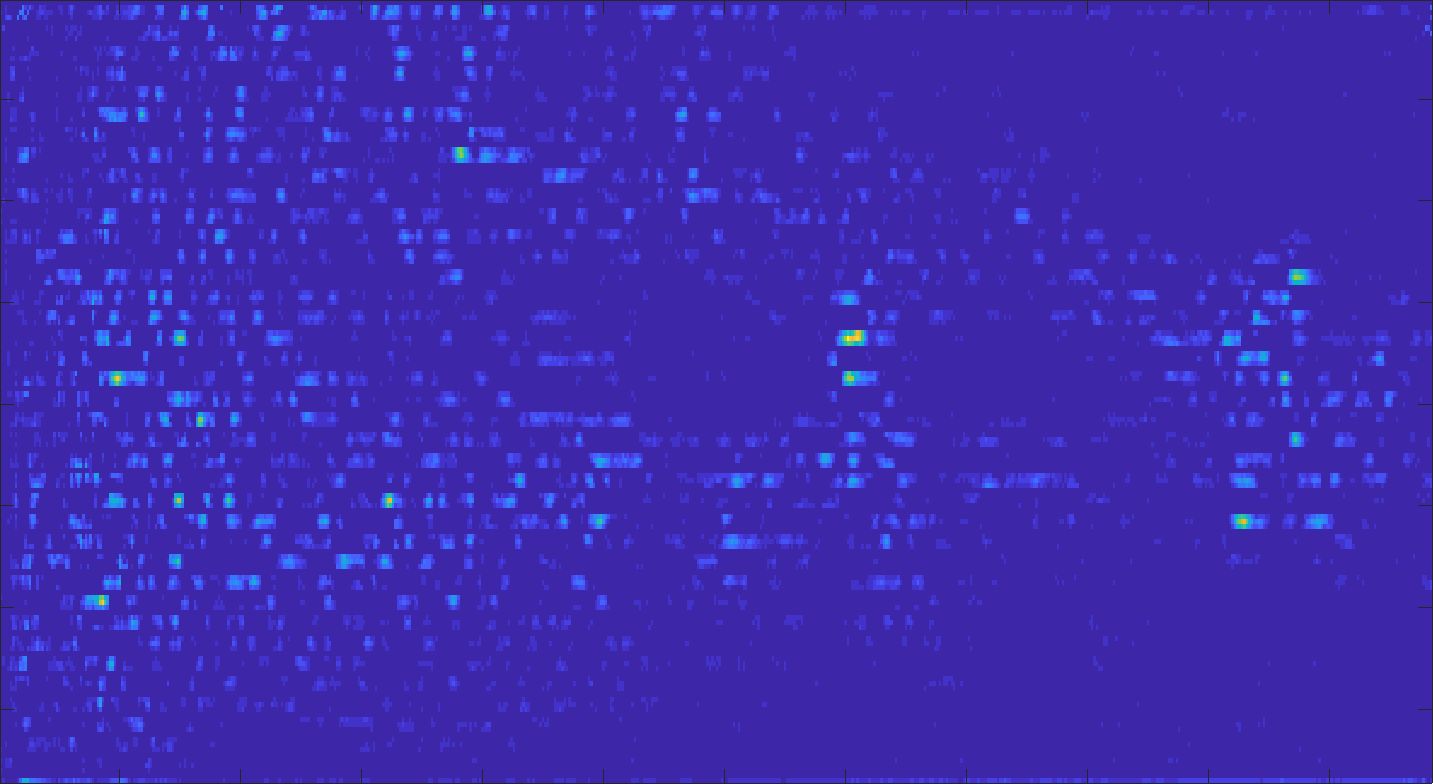

We train each learning-based network (custom-WDSR) with 1.5K images, where the input is the outcome of the selected up-sampling method (i.e., Cubic convolution), and the target is the original high-resolution image. Indeed, input and target images have the same resolution, as the reconstruction of the missing lines has been already performed by Cubic convolution. Figs. 3, 4, and 5 show the results of the network prediction, compared with the input and the target images. Target images correspond to spatial high-resolution images; input images are the outcome of the up-sampling interpolation, which is applied to spatial low-resolution images (i.e., the down-sampling along the lateral direction of high-resolution images); prediction images represent the output of the neural network.

Our framework visually improves the results, in terms of blurring and artefacts. This result is more evident in the magnification of the ear of the foetus (Fig. 3), the mitral valve (Fig. 4), and the mass edges (Fig. 5). Fig. 6 shows the error image of the three anatomical districts with both 2X and 4X up-sampling factors, with the maximum error in the scale . The error is more evident in the contours of the anatomical structures; moreover, the abdominal district shows a smaller error than the cardiac and obstetric ones. We underline that the view for each image is scaled to its maximum, to improve the visualisation of the error.

We address both the comparison among state-of-the-art algorithms that are used for the selection of the up-sampling method of our framework and the comparison of our results with previous work. Among up-sampling STAR methods, we test four methods belonging to different classes: Cubic Convolution [Key81], a kernel-based interpolating method; Enhanced Deep Residual Networks - EDSR [LSK+17], a learning-based method trained on generic images; Enhanced Super-Resolution Generative Adversarial Network Plus - ESRGAN+ [RR20], a learning-based GAN method, specialised on US images with a dedicated training; Single Image Super Resolution - SISR [PE14], an up-sampling method which exploits sparse representations. We evaluate the up-sampling results of the selected methods on different anatomical districts and resolutions: obstetric district with 0.5X down-sampling (Fig. 12); abdominal district with 0.25X down-sampling (Fig. 13). Fig. 14 shows the error image between target and SOTA super-resolution on both 2X and 4X up-sampling, with the maximum error value in the range : Cubic convolution has visually the best results in terms of approximation error. Furthermore, our method improves the error image results with respect to Cubic convolution, improving the approximation of the target image, including the maximum error. All the error images of each up-sampling factor are represented with the same colour scale to better visualise the differences among the methods.

Fig. 15 shows the results of the prediction of the network, compared with the input and the target denoised images of the obstetric district. Our framework visually improves the results, in terms of blurring and artefacts. Fig. 16 shows the error image of our prediction with respect to the target denoised image, for both 2X and 4X up-sampling. The error is mainly distributed on the edges of the anatomical structure. Furthermore, the maximum error of the 2X up-sampling is 6 in the range of , showing us that our method accurately predicts the target if soft denoising is applied before up-sampling.